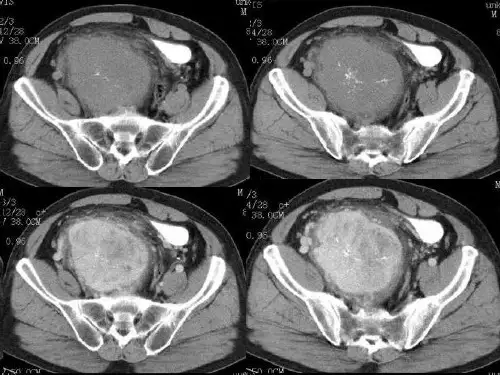

患者在全麻下行“右上纵隔多发巨大肿物切除 术”,术中胸腔镜探查见:右上后纵隔见4个囊实 性肿瘤,从上往下依次分别为8cmX6cmX5cm, 4cmX3cmX2cm,3cmX2cmX2cm,6cmX5cmX4cm 大小。均凸向右侧胸腔,压迫右上肺,基底均较 宽,与胸顶、后胸壁、右侧纵隔及胸骨右侧分界 不清,最高位巨大肿物与右上肺稍粘连,与右锁 骨下动静脉粘连明显;最低位巨大肿物基底部深 入胸骨右侧,面积约3cmX2cmX2cm大小。术中考 虑右上纵隔多发巨大肿物,性质待定

病例4男性,47岁,反复右胸闷、气喘半个月 , 拟“右上肺占位并肺不张、前纵膈占位”收入院

1.前纵膈占位,未见FDG浓聚,考虑良性 病变可能,畸胎瘤?请结合临床。 2.右上肺占位,异常高代谢,考虑恶性病 变; 3.双侧胸腔积液; 4.心包积液。